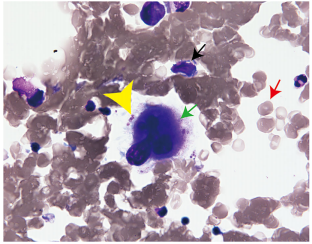

凝血试验显示整个过程中的纤溶亢进。一个月后,随着血小板计数恢复到142×10^3/uL,开始使用德瓦鲁单抗(图2a)。在开始使用德瓦鲁单抗后不久,血小板减少症出现在最低水平55×10^3/uL,尽管血红蛋白浓度和白细胞计数正常。由于血小板减少症没有改善,德瓦鲁单抗在五个周期后停止。由于血小板相关IgG(PA-IgG)水平约为正常水平的两倍,因此进行了骨髓检查。骨髓检查正常,病理学未见肿瘤浸润、母细胞增生、骨髓发育不良或骨髓纤维化。仅显示巨核细胞缺失(图3),这与特发性血小板减少性紫癜(ITP)不一致。巨核细胞周围几乎没有血小板。在骨髓涂片中,有核细胞计数为56000/uL,表明轻度发育不全。髓系:红系(M:E)比值为1.48。髓系、红系和淋巴系的比例分别为53.2%、32.6%和12.8%。没有进行骨髓活检。患者接受了30mg泼尼松龙治疗,逐渐减量至10mg(图2b)。六个月后,血小板计数恢复到110×10^3/uL的水平。

图3. 高倍镜下骨髓标本的发现。骨髓标本包括所有三种类型的造血细胞,如髓系、红系和巨核细胞系。巨核细胞明显减少,周围有少量血小板。黑色、红色和绿色箭头分别表示髓系细胞、红系细胞和巨核细胞。箭头代表血小板